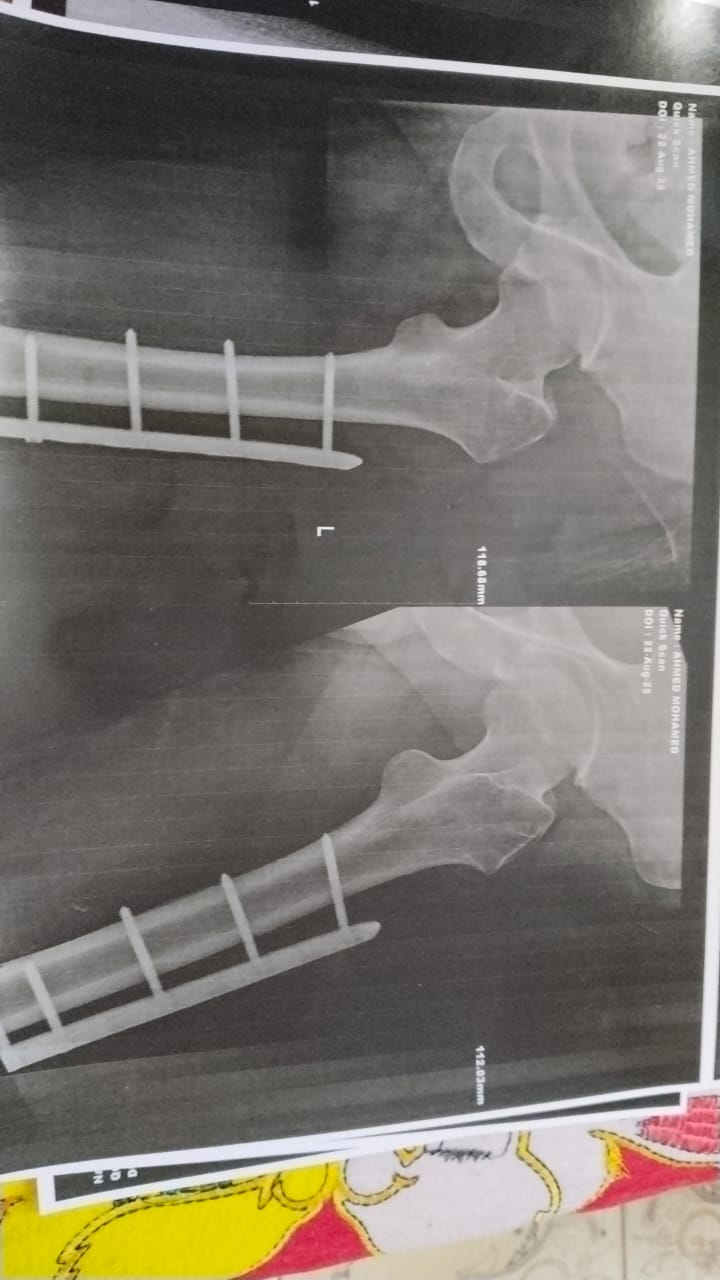

وأضاف أحد مصابي حادث أسيوط، الذي راح ضحيته شخصين وأصيب 31 آخرين، تعرضت لإصابات بالغه نتيجة الحادث، وخضعت لتلقي العلاج بمستشفى الإصابات والطوارئ الجامعي بأسيوط، ولكن تعرضت لخطأ طبي نتيجة الخضوع لإجراء عملية جراحية بالساق.